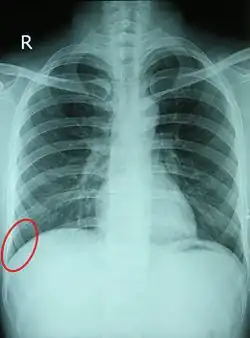

![]() Chest X-ray of a 30-year-old healthy man, with the costodiaphragmatic recess label in red ellipse | |

Pleural effusions collect in the costodiaphragmatic recess when in standing position,[2] and present on plain X-rays as "blunting" of the costophrenic angle.

In anatomy, the costophrenic angles are the places where the diaphragm (-phrenic) meets the ribs (costo-).

Each costophrenic angle can normally be seen as on chest x-ray as a sharply-pointed, downward indentation (dark) between each hemi-diaphragm (white) and the adjacent chest wall (white). A small portion of each lung normally reaches into the costophrenic angle. The normal angle usually measures thirty degrees.

Pleural effusion

With pleural effusion, fluid often builds up in the costophrenic angle (due to gravity). This can push the lung upwards, resulting in "blunting" of the costophrenic angle. The posterior angle is the deepest. Obtuse angulation is sign of disease.

Chest x-ray is the first test done to confirm an excess of pleural fluid. The lateral upright chest x-ray should be examined when a pleural effusion is suspected. In an upright x-ray, 75 mL of fluid blunts the posterior costophrenic angle. Blunting of the lateral costophrenic angle usually requires about 175 mL but may take as much as 500 mL. Larger pleural effusions opacify portions of the hemithorax and may cause mediastinal shift; effusions > 4 L may cause complete opacification of the hemithorax and mediastinal shift to the contralateral side.